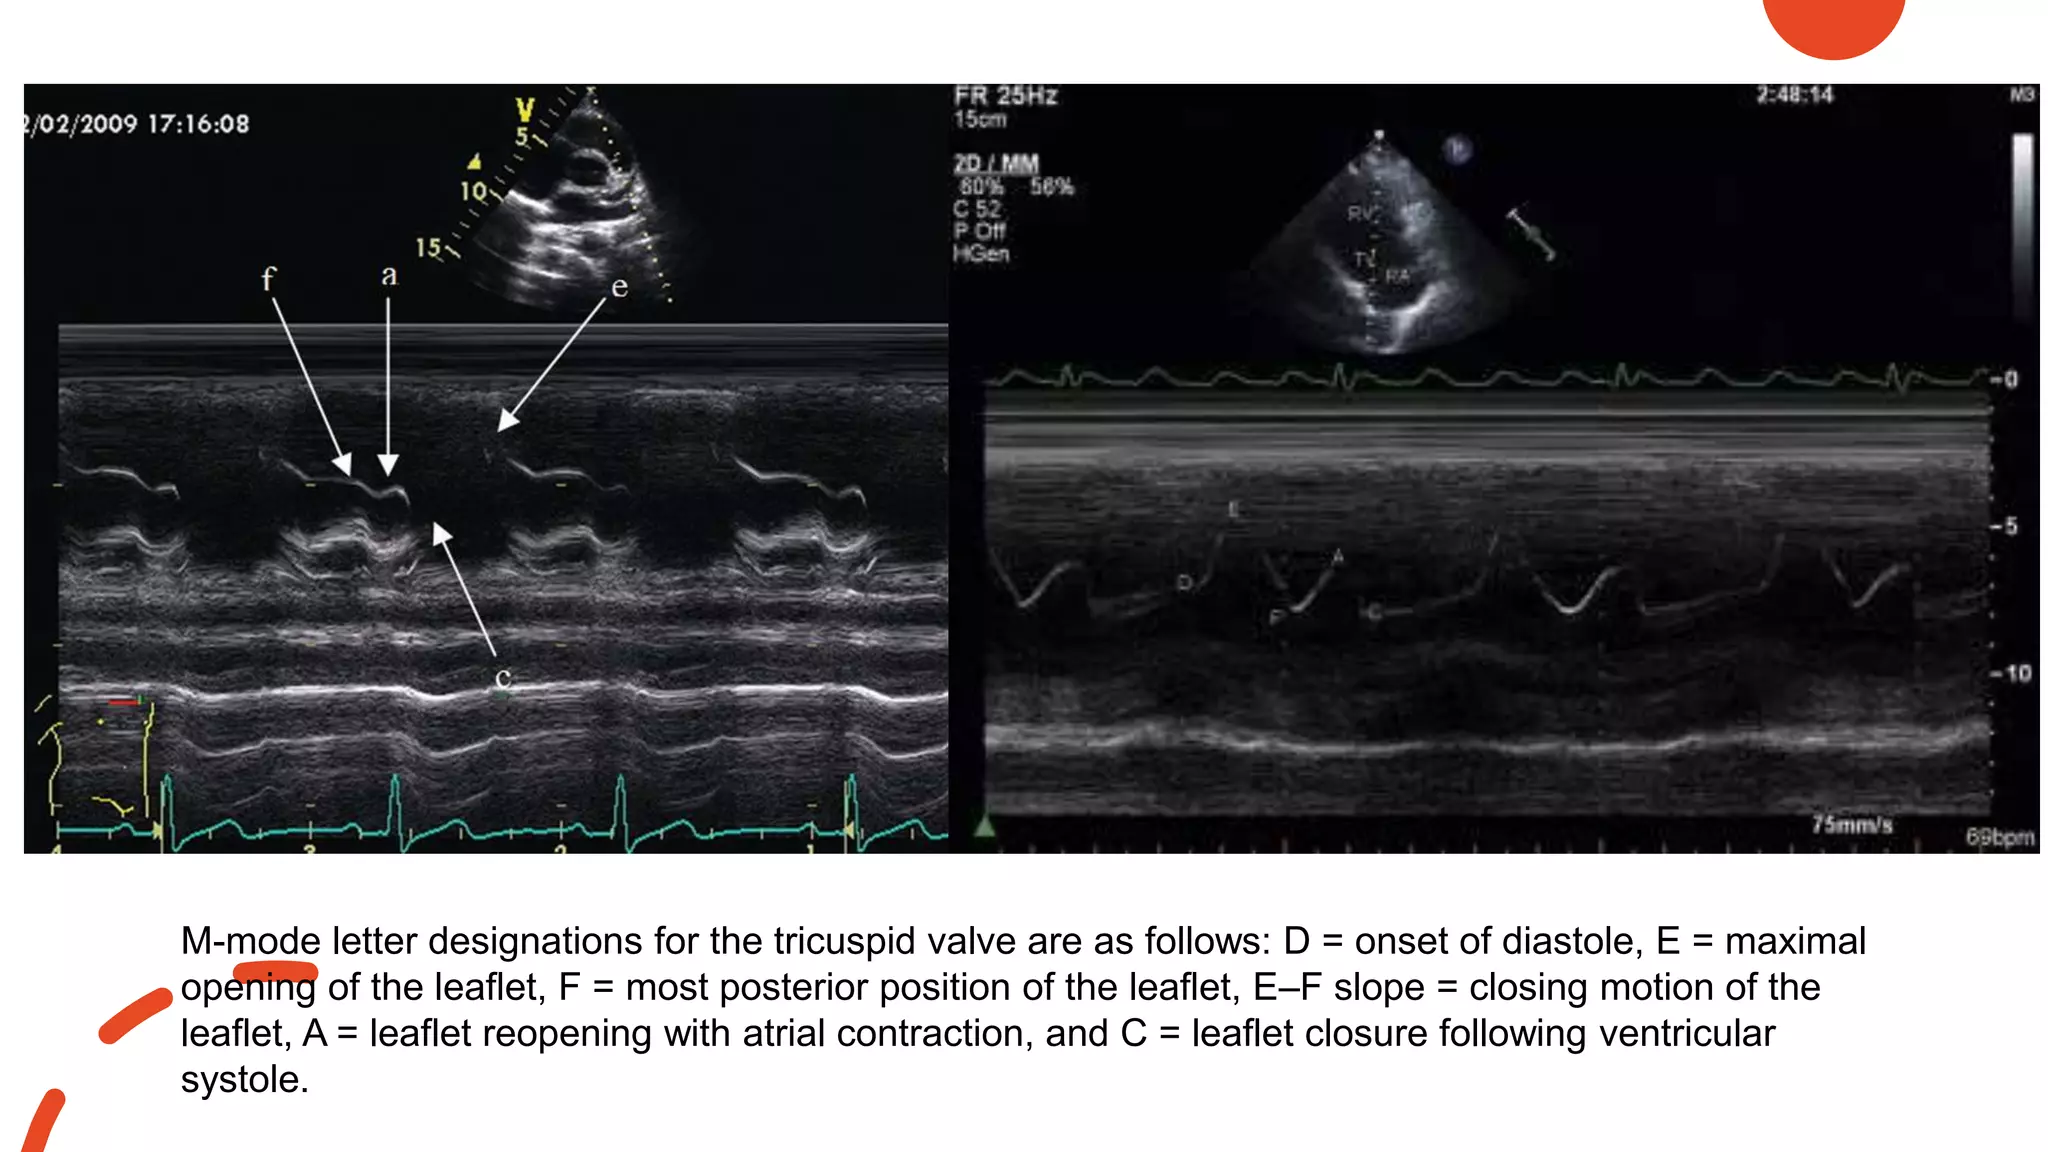

Normal M-Mode Examination of

the Tricuspid Valve

• The normal m-mode recording of

the tricuspid valve is obtained from

the right ventricular inflow view

• Usually, only the anterior leaflet of

the tricuspid valve is transected by

the m-mode cursor

M-mode letter designations for the tricuspid valve are as follows: D = onset of diastole, E = maximal

opening of the leaflet, F = most posterior position of the leaflet, E–F slope = closing motion of the

leaflet, A = leaflet reopening with atrial contraction, and C = leaflet closure following ventricular

systole.

• 77.

M-mode letter designationsfor the tricuspid valve are as follows: D = onset of diastole, E = maximal opening of the leaflet, F = most posterior position of the leaflet, E–F slope = closing motion of the leaflet, A = leaflet reopening with atrial contraction, and C = leaflet closure following ventricular systole.